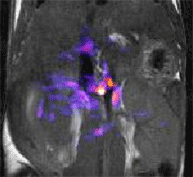

Functional imaging of the mouse pancreas during glucose stimulated insulin secretion (GSIS) by MRI. The colored overlay on this image of the mouse abdomen shows the tissue regions that become T1 enhanced by the Zn2+ ion sensor, GdDOTA-diBPEN, after a bolus injection of glucose to stimulate insulin secretion. Zn2+ is released from beta cells along with insulin and the free Zn2+ is detected by the MRI responsive sensor.

My second interest is the development of new molecular imaging agents that respond to physiology or metabolism and report that information by MRI. We have been involved with development of gadolinium complexes as non-specific extracellular MRI contrast agents since the early 1980’s and are now heavily involved with the next generation smart agents that respond to physiological parameters such as pH or for imaging the tissue distribution of the important metabolite, glucose. A new class of MR contrast agents was also recently discovered by our group that can be activated by specific RF pulses, called PARACEST agents. This new class of agents offers the potential to image a much broader spectrum of physiological/biochemical parameters including cell redox, enzyme activity, and tissue hypoxia.